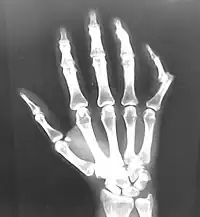

Raios X geralmente são realizados para confirmar o diagnóstico e detectar qualquer fratura que possa ter ocorrido no momento da luxação. Uma luxação é facilmente vista em um raio-X.